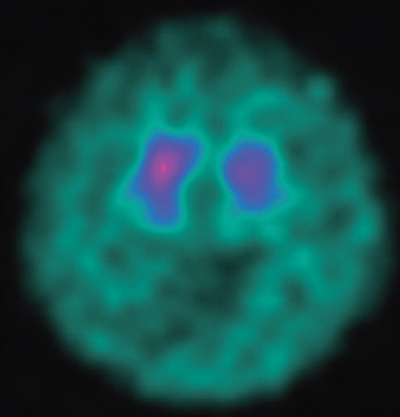

表情は乏しいが、眼球運動は正常で眼振は認めない。右優位の筋強剛と無動を認めるが、振戦を認めない。四肢の腱反射は正常で、Babinski徴候は認めない。ドパミントランスポーター SPECTを別に示す。

最も考えられるのはどれか。

a. Parkinson 病